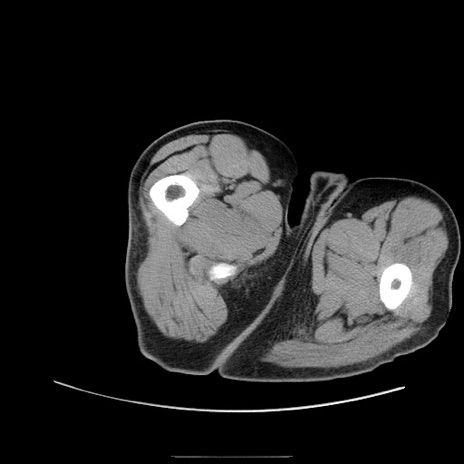

症例22(横断像)

【症例】50歳代男性

【主訴】腹痛

【現病歴】AVMからの被殻出血のため回復期リハ病棟入院中。 本日午後3時頃急に下腹部痛が出現した。

【既往歴】AVM、被殻出血、虫垂炎、高血圧

【身体所見】意識晴明、左半身不全麻痺、会話の理解は良好、36.5°C、腹部:膨隆、全体に板状硬、下腹部正中に圧痛点あり、反跳痛-、筋性防御不明、右下腹部にope scar

【データ】WBC 9400、CRP 0.06